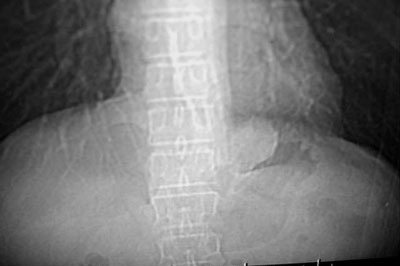

左下叶后基底段内胸主动脉旁可见一类梭形团块状影,边界较清楚,其内有小结节样高密度钙化影,肿块与胸主动脉可见条状影相连(见下图).

诊断:左下叶肺段隔离症.

支持向医生老师图示的意见,考虑隔离肺。不过,病灶内应该不是钙化,而是光标。